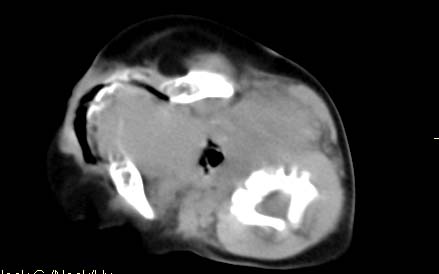

男,26天,发现左侧颈部包块5天,质较硬,患儿不哭不吵,无明显发热,头向右侧歪斜,其父母诉患儿出生时正常,昨天查血象wbc19.4×10的9次方/l,b超考虑来源于甲状腺的恶性肿瘤,我科认为肿块内有低密度区,而且病程发展较快,血象高,考虑炎性病变可能大。患儿年龄太小没做增强。请大家提出高见。

男,26天,发现左侧颈部包块5天,质较硬,患儿不哭不吵,无明显发热,头向右侧歪斜,其父母诉患儿出生时正常,昨天查血象wbc19.4×10的9次方/l,b超考虑来源于甲状腺的恶性肿瘤,我科认为肿块内有低密度区,而且病程发展较快,应该首先排除血肿,其次考虑感染

随访结果:炎症(患儿经过一星期抗炎治疗后颈部包块明显缩小,现已经正常)。